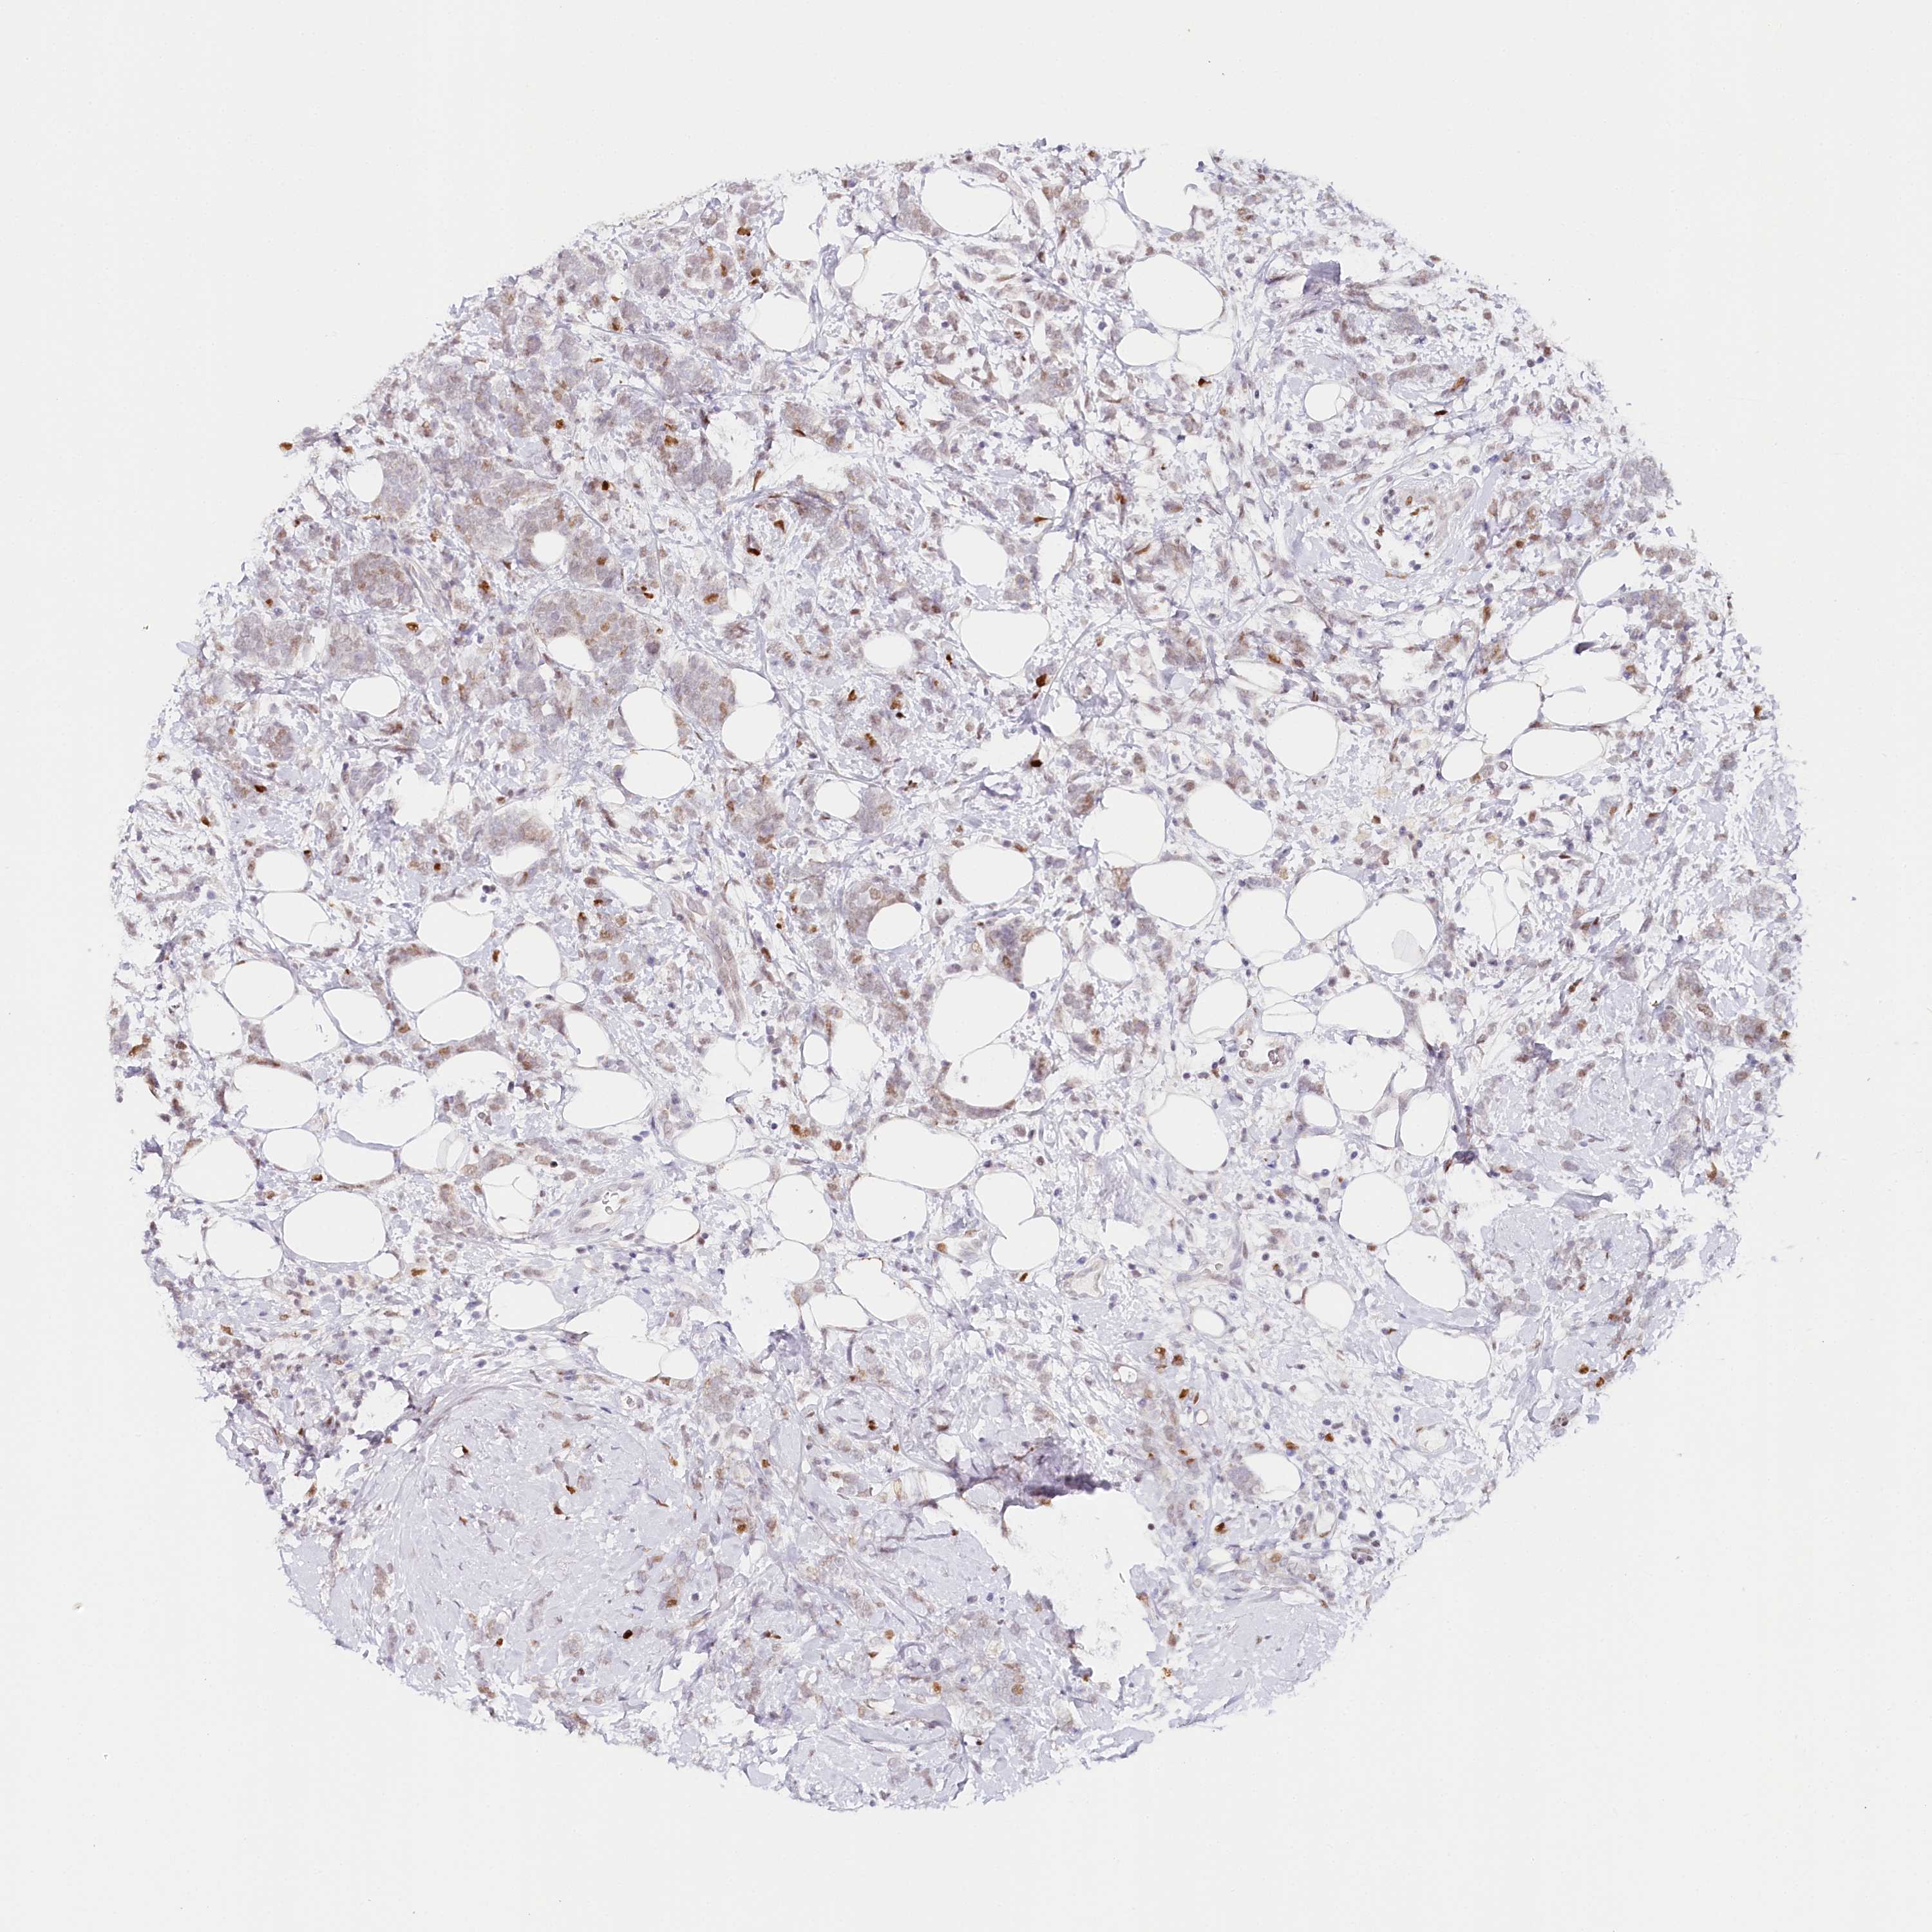

CANCER BREAST CANCER Show tissue menu

BRCA TCGA BRCA VALIDATION PROTEIN EXPRESSION